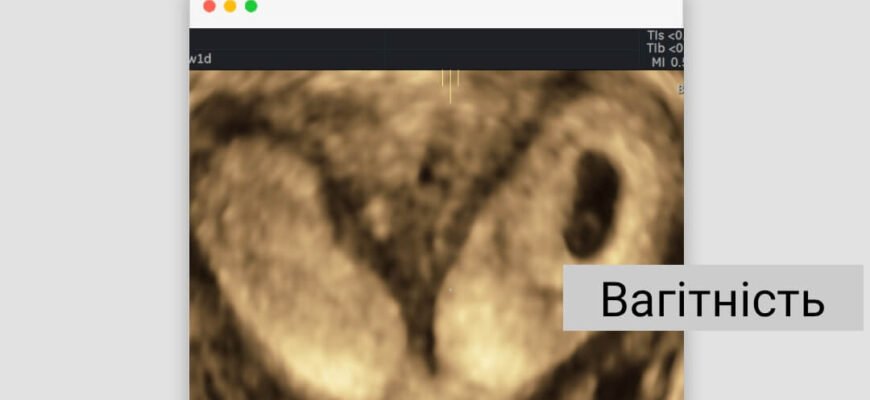

Рання діагностика здійснюється через УЗД, МРТ або гістероскопію. Важливо звертатися до професіоналів, щоб виявити, домогтися точного діагнозу. Часто жінки запитують самі себе: дворога матка чи можна завагітніти – це одне з найбільших питань, яке постає при такому діагнозі.

Вагітність при дворогій матці

- Можливість зачаття присутня, навіть якщо умови не ідеальні.

- Ризик невиношування чи передчасних пологів підвищений.

- Пологи найчастіше проходять шляхом кесаревого розтину.